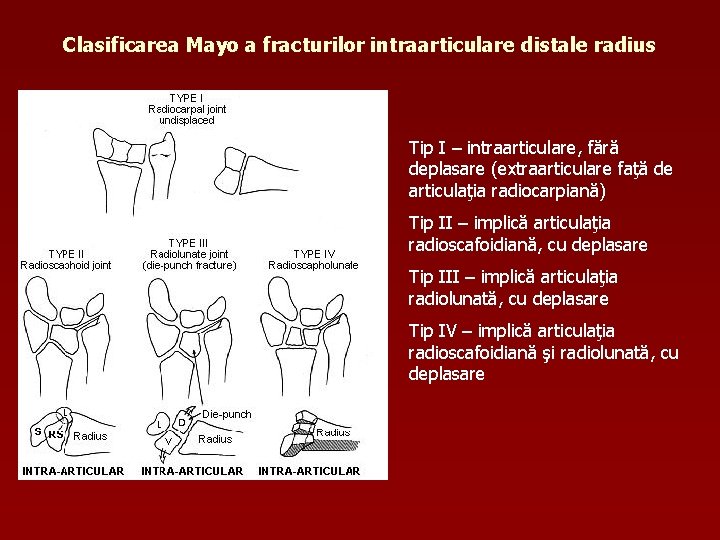

Clasificarea Mayo a fracturilor intraarticulare distale radius Tip I – intraarticulare, fără deplasare (extraarticulare faţă de articulaţia radiocarpiană) Tip II – implică articulaţia radioscafoidiană, cu deplasare Tip III – implică articulaţia radiolunată, cu deplasare Tip IV – implică articulaţia radioscafoidiană şi radiolunată, cu deplasare

Mayo II Mayo IV